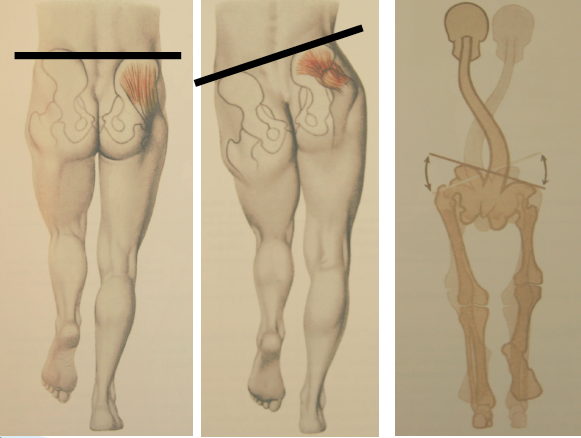

Quel est ce signe?

C’est le signe de Trendelenbourg qui témoigne d’une atteinte du moyen fessier. C’est la boiterie classique d’une arthrose de la hanche.

On penche du même coté que la hanche qui est malade.

Pcq pour être droit ça augmente la pression sur la tête fémoral pis pour les gens qui ont de l’arthrose ça fait mal